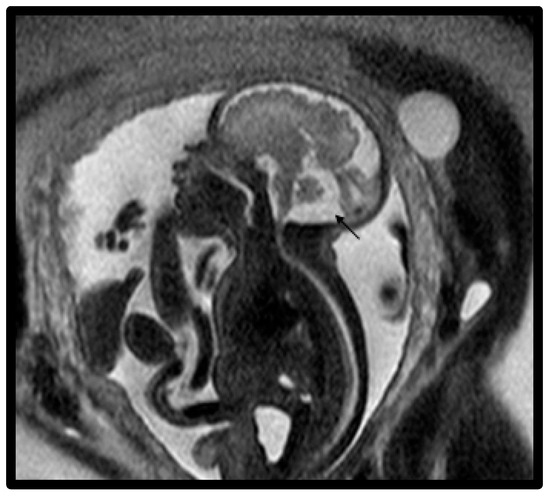

| 3 | Classic DWM | Absent cerebellum, large PF, dilated 4th ventricle, enlarged CM, severe hydrocephalus, massive DW cyst, small and thin brainstem. | 31 | Normal karyotype and microarray | Live birth, died before discharge. | Preterm C/S delivery, intubated in DR due to poor tone, no respiratory effort, central cyanosis, bradycardia, and massive macrocephaly. EEG showed global neuronal dysfunction. Imaging showed hydranencephaly. Respiratory failure with apnea and respiratory acidosis. Infant was compassionately extubated and died on day of life 7. Autopsy showed macrocephaly, posterior fossa cyst, severe cerebellar hypoplasia and partial hypoplasia of the brainstem, severe hydrocephalus with severe atrophy of cerebellar cortices, and no deep gray matter structures identified. Abnormal heart congenital polyvalvular disease moderate type was diagnosed with stenosis of tricuspid, mitral and aortic valves, and atypical hypertrophic cardiomyopathy. Liver with islands of extramedullary erythropoiesis. |

| 4 | Classic DWM | Absent cerebellum, enlarged PF, dilated 4th ventricle, enlarged CM, severe hydrocephalus, massive DW cyst, encephalomalacia or schizencephaly, hypoplastic brainstem, thin cerebral hemispheres. | 33 | ---- | Outborn | Postnatal course not available due to outborn status. |